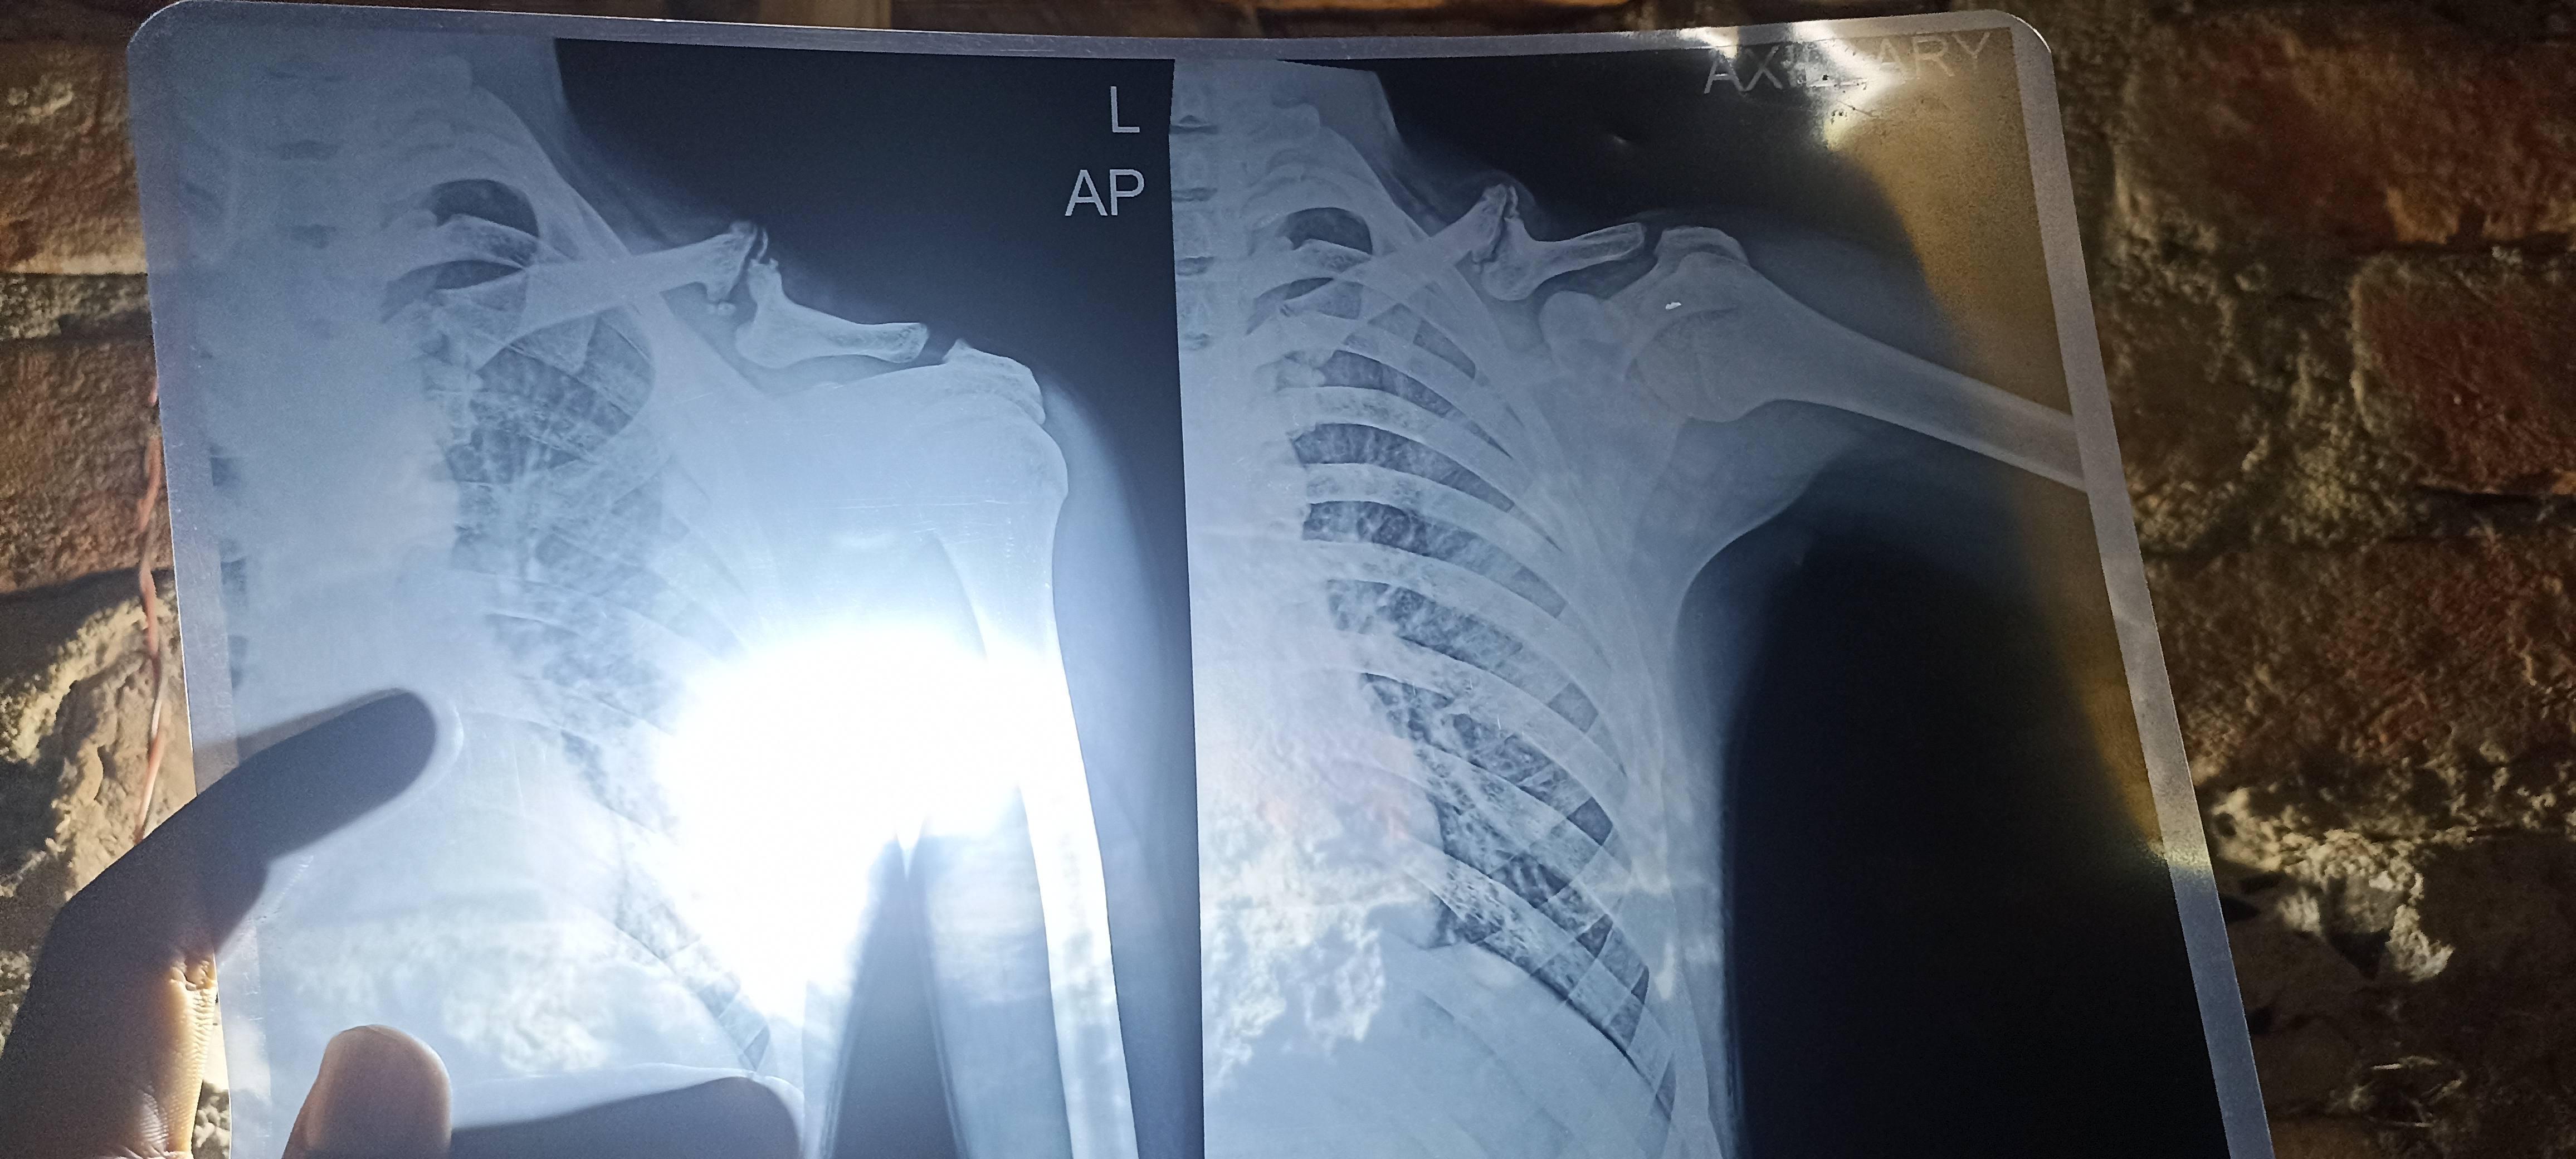

Sir mere x-ray me muje kuch batao

Solder me problem h kuch batao